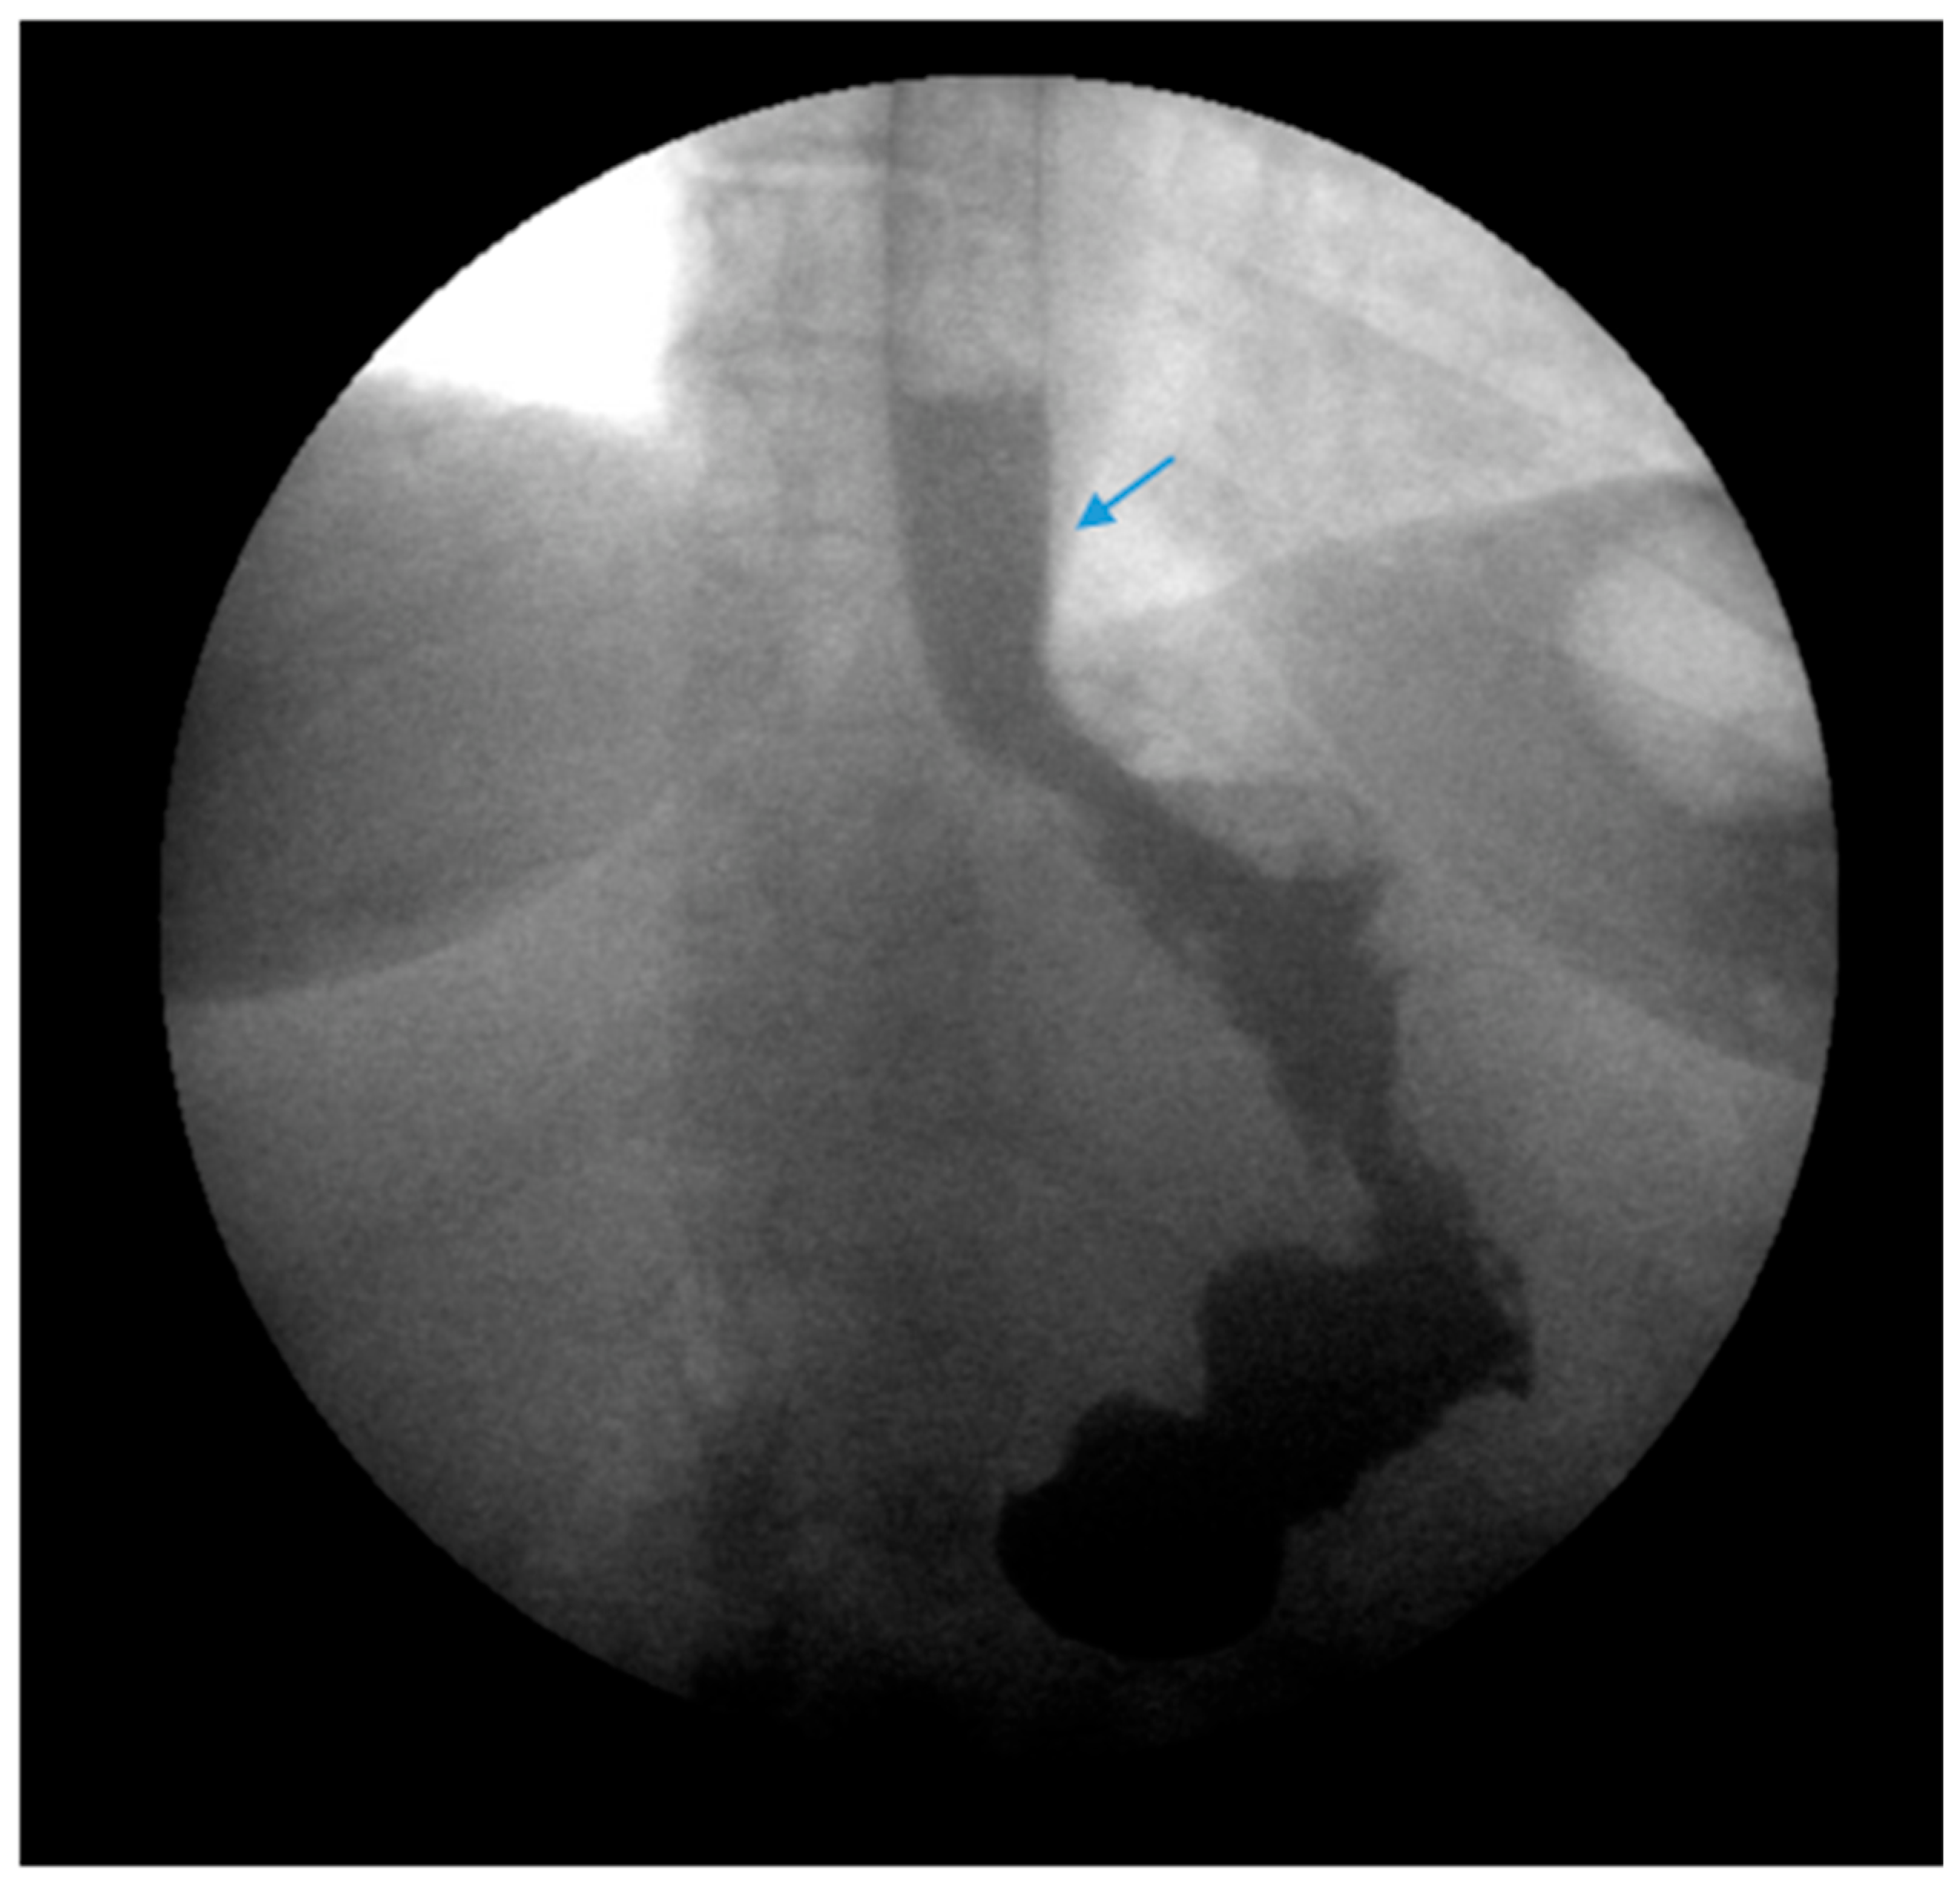

Endoscopic balloon dilation (EBD) has been shown to be a safe and efficacious modality for gastric sleeve stenosis (GSS) (Figure 4) [49,50]. A meta-analysis by Chang et al. of 18 studies involving a total of 426 patients revealed an overall success rate of 76% and an average of 1.8 dilations per patient [51]. Proximal GSS had a higher efficacy rate of 90% compared to distal GSS which had an efficacy rate of 70% [51]. Studies in the meta-analysis utilized through-the-scope, controlled radial expansion balloons, pneumatic balloons used for achalasia or a combination of the two [51]. The optimal balloon type, balloon size and the number of dilations required remains unclear [52]. Fully covered self-expanding metal stents (FCSEMS) have been reported to be effective in 70% of cases in which EBD failed though stent migration remains a concern [51,53].

Figure 4.

(Left) An upper gastrointestinal series in a patient post-sleeve gastrectomy with recurrent dysphagia reveals dilation of the gastric sleeve at the cardia (blue arrow) with narrowing and delayed passage of contrast through the middle and distal portions (green arrows) of the gastric sleeve. (Middle) The patient underwent serial endoscopic through-the-scope balloon dilation to 20 mm (blue arrow) with improvement in sleeve stenosis (Right) and dysphagia.